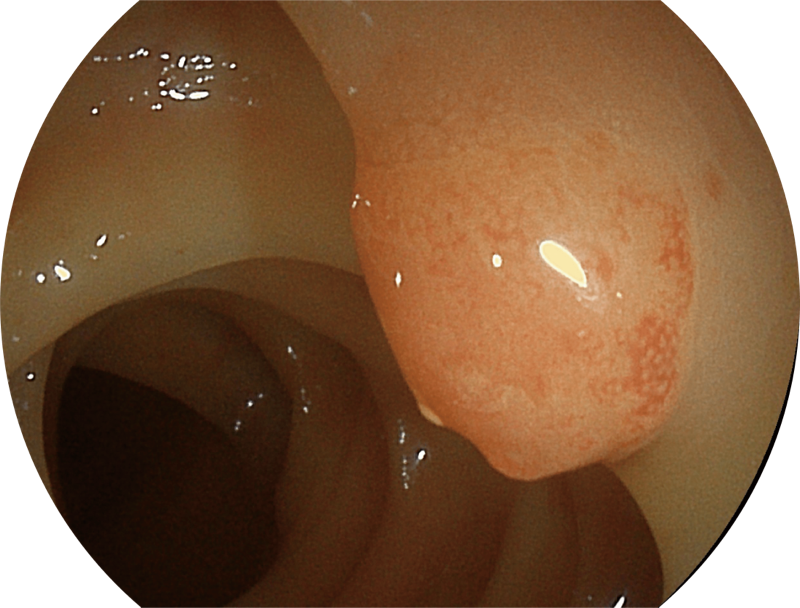

百万级像素高清传感器,1080P全高清视频信号输出,图像清晰。

白光图像

SFI图像